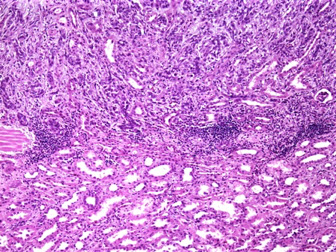

Xanthogranulomatous pyelonephritis

Staghorn calculus, E. coli, Proteus

- the result of suppurative sequela of chronic pyelonephritis

Gross: yellow-grey parenchyma tissue around dilated calyces and pelvices (2/2 staghorn calculi)

Micro: lots of foamy histiocytes c mixed inflam and some MNGCs

- 3 "zones":

Inner zone: neutros, lymphs, plasma cells, histiocytes c lots of necrosis and cholesterol

Middle zone: lymphos and granulation tissue

Outer zone: foamy histiocytes

DDx: clear cell RCC and malakoplakia